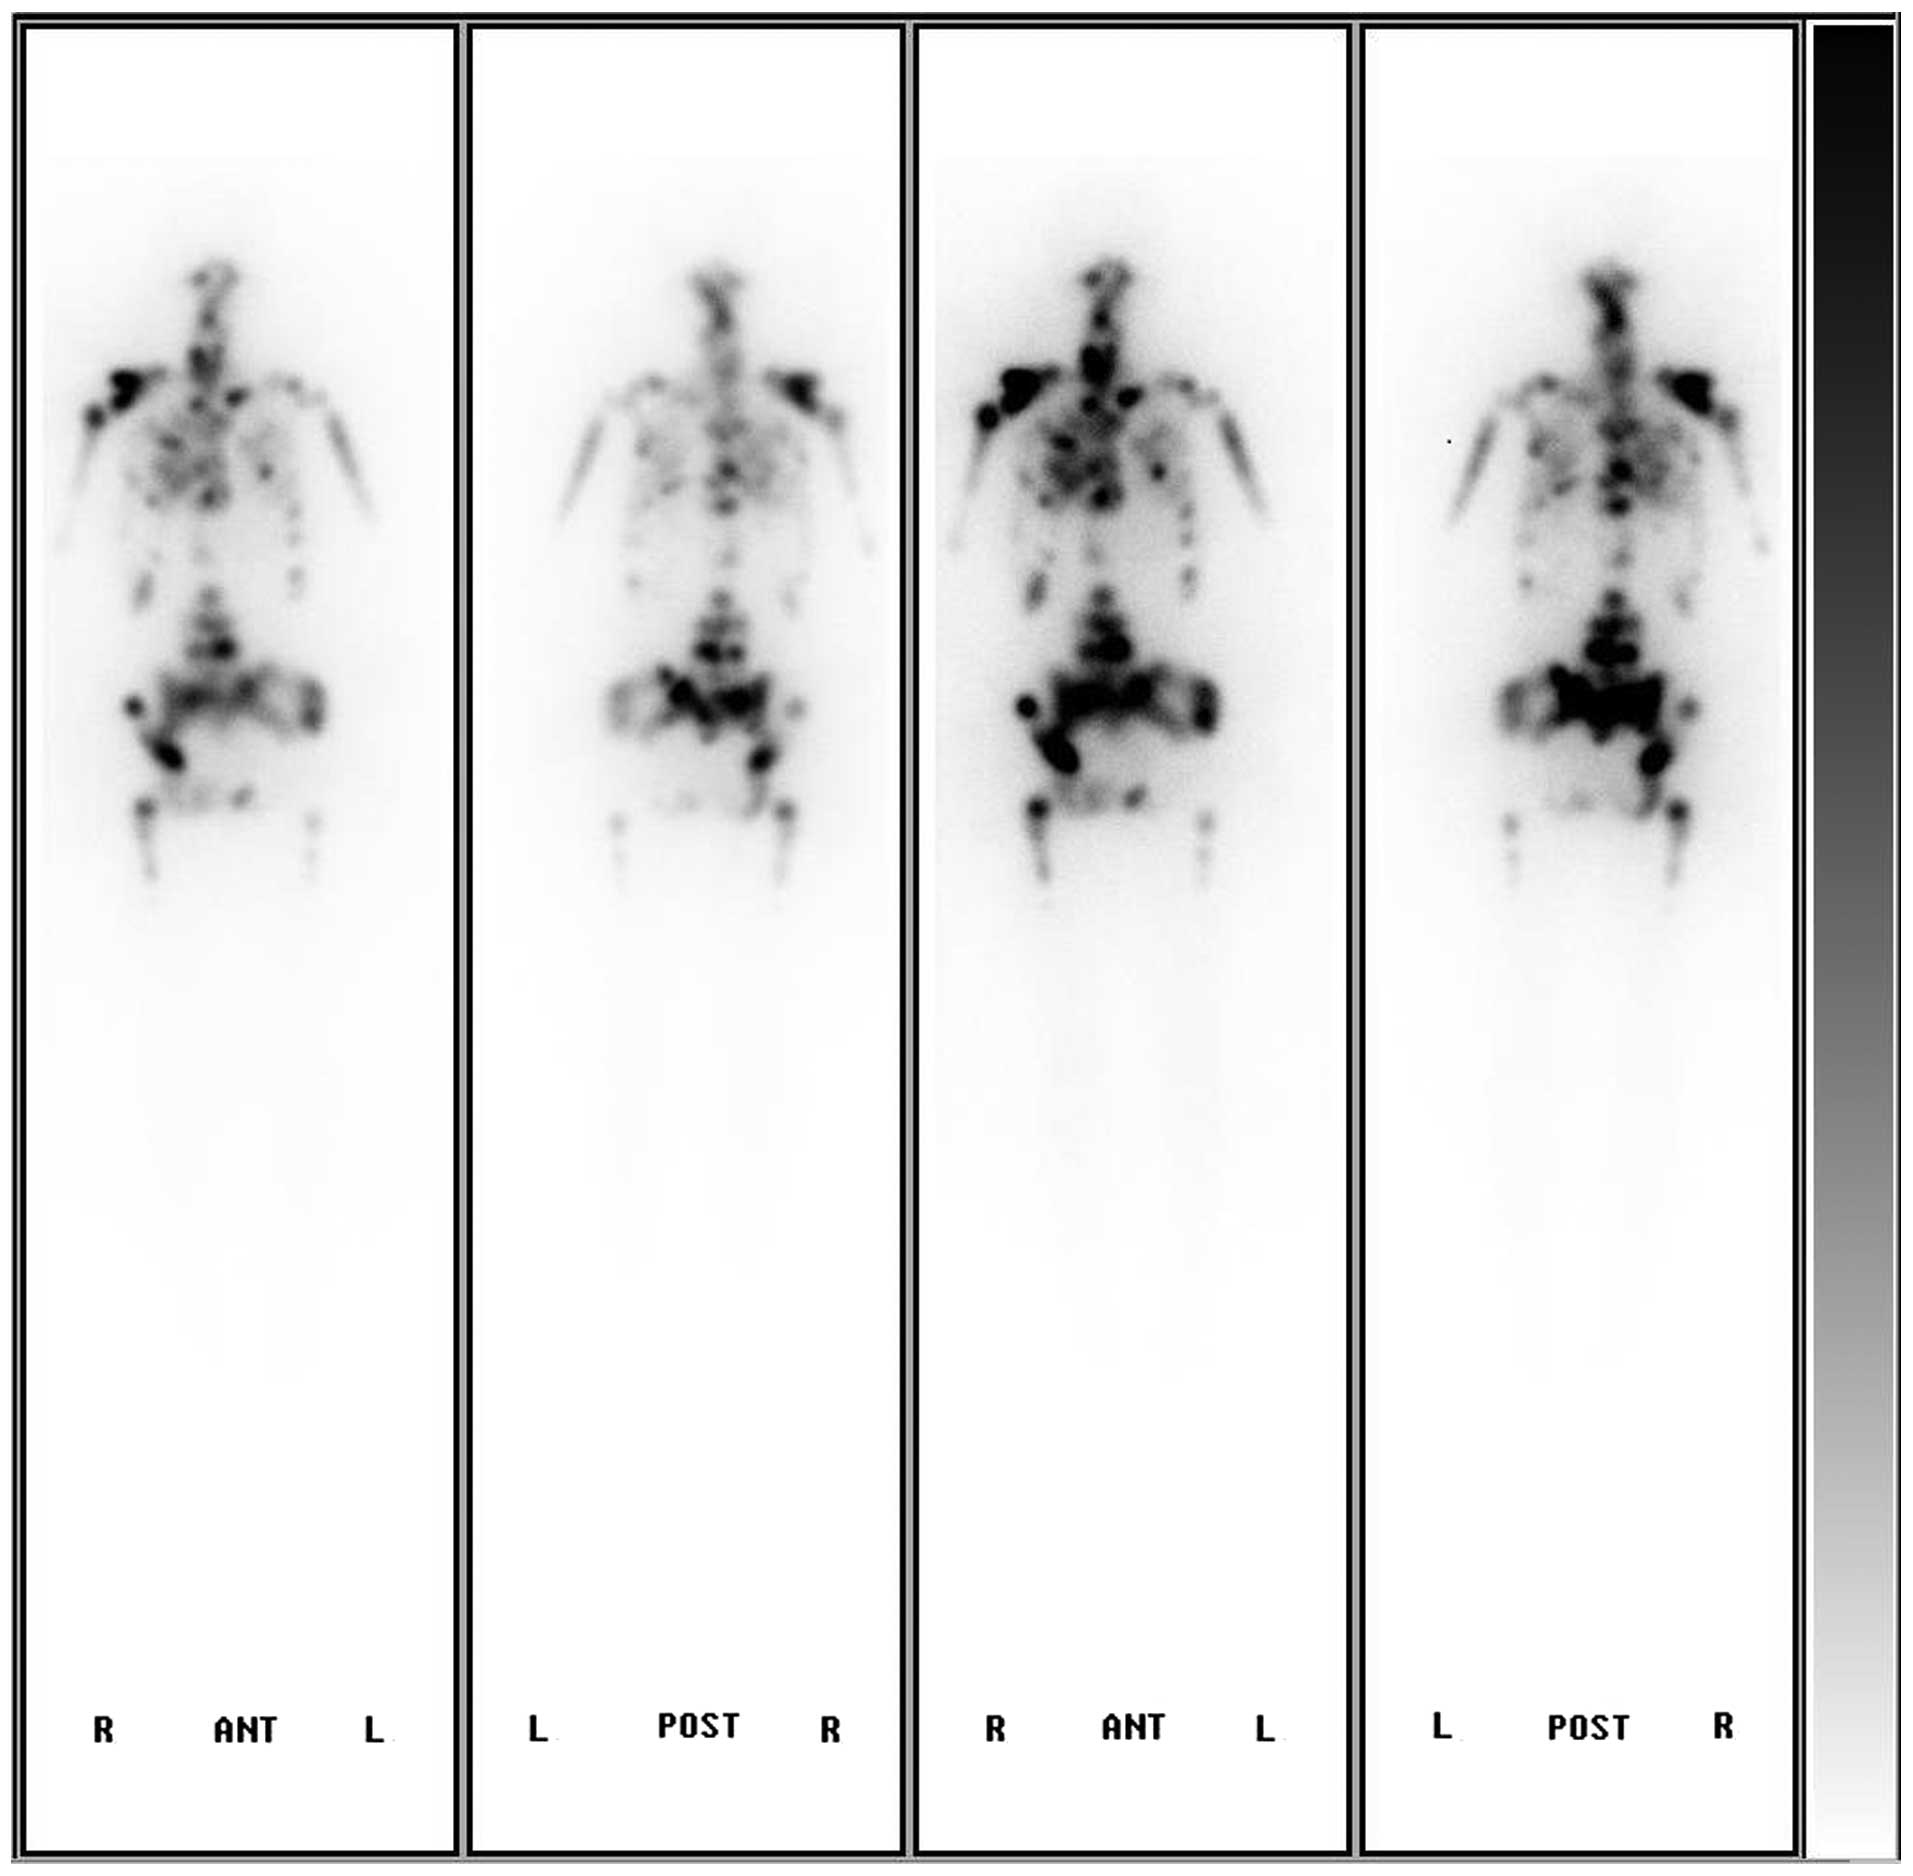

Following the surgery, the patient was given levothyroxine sodium (50 µg/day) and morphine sulfate for analgesia. Two months later, due to an accidental fall, the patient's physical activity was limited as a result of coccyx pain. In April, radioiodine treatment with thyroid hormone withdrawal (THW) was carried out (3.7 GBq 131I). The subsequent post-therapeutic whole-body scintigraphy showed extensive uptake in the basic thyroid deposits, most bones and both lungs (Fig. 5). Three months after the treatment, the patient succumbed to cachexia. The thyroglobulin (Tg) level had always remained >300 (0–55) ng/ml, from the presurgical stage to during and following THW. The Tg antibody level was normal.

Figure 5.

Subsequent post-therapeutic whole body scintigraphy showing extensive uptake of 131I in basic thyroid deposits, most bones and both lungs. A, anterior; P, posterior.